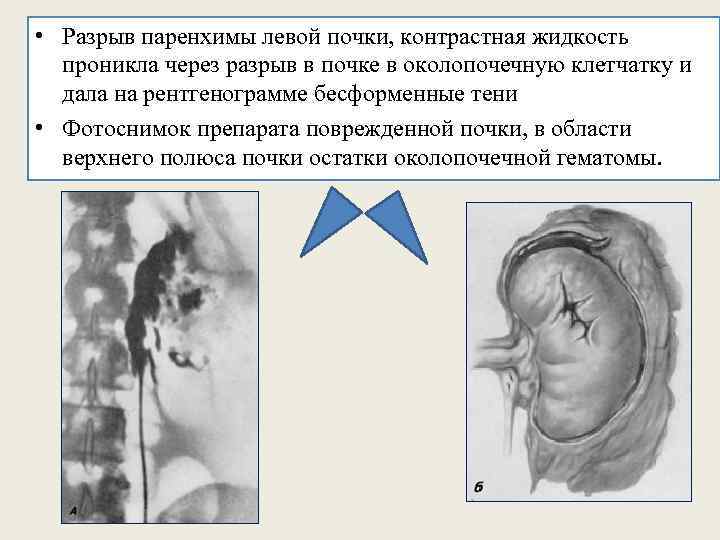

Экскреторная урография • Затеки контрастного вещества • Сдавливание чашечек и лоханки

• Разрыв паренхимы левой почки, контрастная жидкость проникла через разрыв в почке в околопочечную клетчатку и дала на рентгенограмме бесформенные тени • Фотоснимок препарата поврежденной почки, в области верхнего полюса почки остатки околопочечной гематомы.